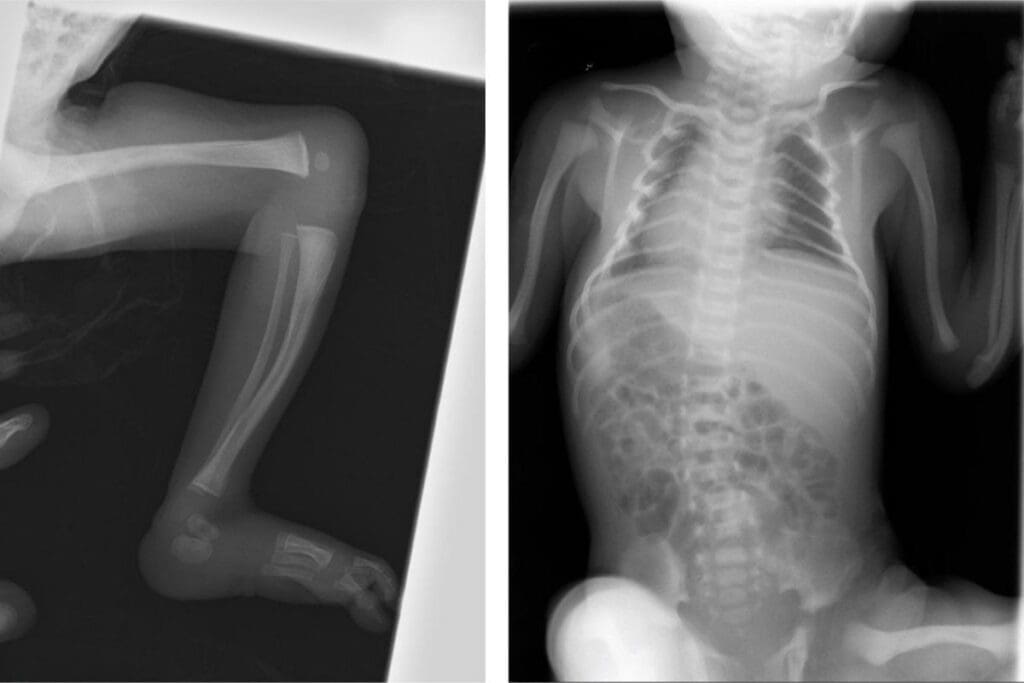

Limb Malformations

Limb malformations are problems with arm or leg development. They can be mild, like clubfoot, or severe, where limbs are missing. Limb malformations can greatly affect how well someone can move and their quality of life.

Diagnosis and Detection Methods

Postnatal Diagnosis

After birth, postnatal diagnosis is vital for finding congenital anomalies. Doctors do physical checks to spot visible issues. For hidden problems, X-rays, ultrasound, and MRI are used.

Quickly finding congenital anomalies after birth is key to starting the right treatments. This can greatly help children with these conditions.